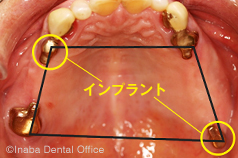

顎が極端に吸収していて入れ歯を吸着できない場合は、お口の周りの筋肉で支えます。またはインプラントを2本または4本埋入し、入れ歯を特殊な留め具で固定する方法があります。

天然歯とインプラントを組み合わせて、より精度の高い入れ歯を作ることができます。インプラントを除去する前に、ぜひ当院へご相談ください。最善の方法が見つかるはずです。

ほかの歯科医院で奥歯を抜いてインプラントを3本入れる治療法をすすめられました。

でも、手術は怖いので別の方法で治療できますか?

はい、可能です。「テレスコープシステム」の部分入れ歯で、誰にも気づかれず快適に過ごすことができます。

通常、欠損部(歯がないところ)の治療はインプラントもしくは“部分入れ歯”になります。

インプラントを避けた場合、“部分入れ歯”という選択肢になりますが保険適用の部分入れ歯は金属のバネが見えてしまいますし、不安定なため硬い物はなかなか食べられません。

残っている歯に金属冠を被せ、その上に入れ歯を装着します

当院おすすめの部分入れ歯は、入れ歯先進国ドイツの方法を忠実に守り正統派の「テレスコープシステム」を採用しています。

無理な手術は行わず、残っている個々の歯へ負担を最小限に抑えながら装着できるのが特長です。

金属のバネ(クラスプ)を一切使用しないため、入れ歯であることを誰にも気づかれることはありません。

装着感も良く、硬いものも食べられます。

定期的にメンテナンスを行うことで長い間使用できます。

インプラントをお考えであれば、入れ歯を取り外す必要がなくなるのも事実です。

しかし、骨が少ない場合は新たに骨を作る手術が必要になるため、患者様への負担が大きくなるのも否めません。

また、部分入れ歯とインプラントを併用することで、パラタルバーや金属床の面積を小さくすることができます。